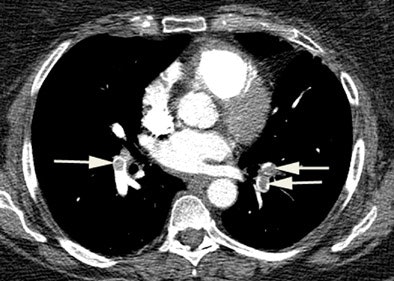

| CT pulmonary angiography shows bilateral acute pulmonary emboli (arrows). Image courtesy of Dr. Phillip Boiselle. |